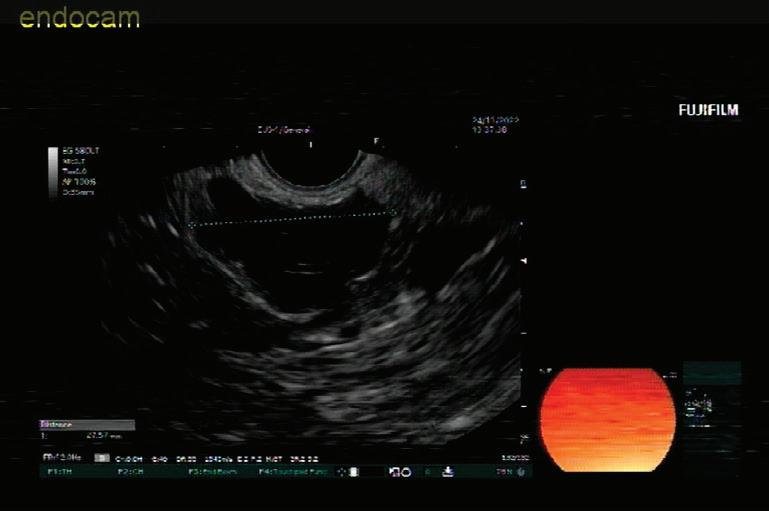

48 КИСТИ НА ПАНКРЕАСАЗНАЧЕНИЕ, ДИАГНОСТИЧНИ ДИЛЕМИ И ИНДИКАЦИИ ЗА ХИРУРГИЯ Н. Шумка, П. Карагьозов

Доц. д-р Цветелина Тотомирова

60 РАДИОФРЕКВЕНТНА АБЛАЦИЯ НА ПАНКРЕАСНИ ТУМОРИ ПОД ЕНДОСОНОГРАФСКИ КОНТРОЛ Й. Петкова, П. Карагьозов, И. Тишков УРОЛОГИЯ